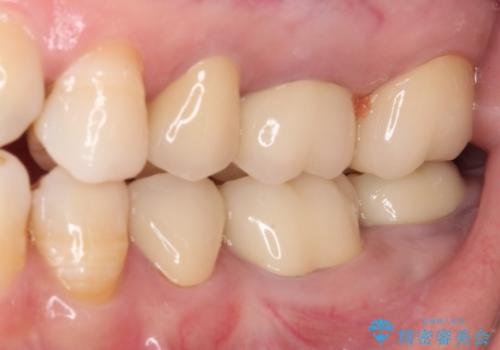

歯冠長延長術を行ったことで、自然な形態かつ清掃性の高いセラミッククラウンを装着することができました。

全顎的に治療を行ったため、治療期間も費用も負担は大きくなりましたが、統一感のある仕上がりとなりました。